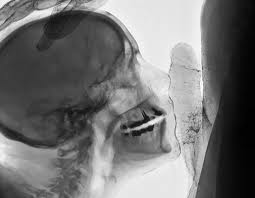

[…] Cuando el artista belga Wim Delvoye realiza imágenes por rayos X de un beso o de actos sexuales, imágenes X por medio de rayos X, no hace otra cosa que apropiarse estéticamente de técnicas científicas a veces de punta, reintroduce la «skiagrafía», excluida antiguamente por la filosofía, y, en la ciencia, lo concerniente al acto sexual, que ella excluye.

Podríamos evocar dos imágenes radiográficas de Wim Delvoye. Estas imágenes tomadas por rayos X, clasificables en la góndola de las imágenes X, poseen una fuerza de verdad extrema. Sin embargo, no donde uno cree, no donde uno ve. Al mostrar un beso o una felación, son para verlas, desde luego, como toda imagen, pero ellas muestran lo que no se ve a simple vista, el interior de los cuerpos en actividad. Ellas nos sitúan en un tiempo posterior al cine pornográfico. El valor del surgimiento del cine pornográfico, si ese valor existe, es en el fondo, haber mostrado algo, una parte de la anatomía que el cine jamás había mostrado, los órganos sexuales en actividad. Las imágenes de rayos X, al ir más allá de la anatomía, van más lejos: van al sexo bajo la piel. Por otra parte, si bien tales imágenes cumplen el sueño de la cámara pornográfica de mostrar desde lo más cerca posible, esto no produce exactamente una mayor excitación sexual. En verdad, las imágenes de Wim Delvoye tienden a mostrar una cosa que no se había visto nunca: cómo funciona el sexo. Sin embargo, debería decirse más bien que lo que estas imágenes muestran, es que no se lo ve. Más aún, que lo normal es que no se lo vea.

[…] Para más exactitud, yo diría que estas imágenes de rayos X, que es posible reunir con el dibujo anatómico de Leonardo en el que se representa el corte de un coito muestran sobre todo que hay algo que no se puede ver: cómo funciona el amor, cuál sería el secreto del sexo. Tal es su dimensión crítica. Ellas se dirigen también a los médicos y a todos para decir que la búsqueda de la transparencia del cuerpo es una fantasía, porque hay algo que jamás se podrá ver ni saber, y por lo tanto dominar: la relación sexual. Pueden ustedes radiografiar el cuerpo, autopsiar el cuerpo, volverlo todo lo transparente que quieran, pero jamás verán con sus ojos el secreto de la relación sexual; o mejor dicho, jamás verán la única verdad que hace saltar los ojos: que no hay nada que ver, que no hay secreto. Esto es lo que, al fin de cuentas, resiste definitivamente a la voluntad del amo de que «eso funcione».